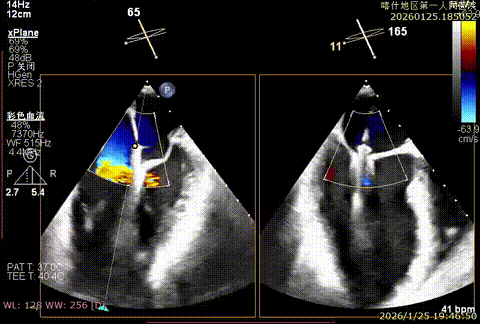

手术策略与手术过程

该例患者为DMR,1,2,3区均见脱垂,主要脱垂位于1区及外交界后叶脱垂,病变解剖结构亦相对复杂。术前制定手术策略:使用3把XTR解决患者瓣叶脱垂与二尖瓣反流。术中首先进行房间隔穿刺,最终穿刺高度4.5cm。穿刺成功后将SGC和XTR-CDS依次送入左心房,通过操控“M”旋钮调节SGC,使二尖瓣夹避开华法林脊并成功定位于2区正上方。在2区进行弹道测试成功后,进行Orientation调整。最终在1区将二尖瓣夹送入左心室,成功捕捞和夹持瓣叶后缓慢关紧夹。第二枚XTR植入2区,采用双拉链技术,从两个夹子中间植入第三枚夹子,固定脱垂区域降低反流。TEE检查见二尖瓣反流程度降低至少量,二尖瓣双孔组织桥稳定,肺静脉逆流改善明显,手术安全结束。

bicomm切面-大脱垂

X-plan 1区后叶脱垂

3D enface脱垂情况

X-plan 反流情况